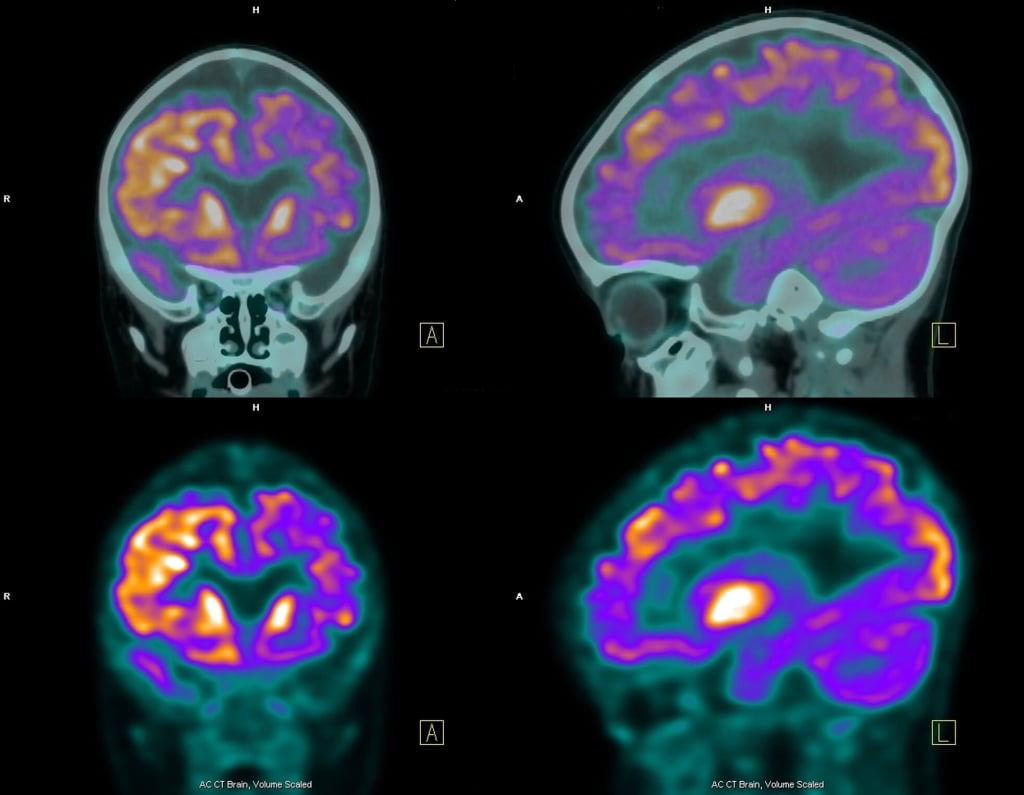

Silvana Franceschetti, responsabile del centro epilessia dell’Istituto neurologico Besta di Milano, aggiunge: «La comparsa di crisi protratte o la ripetizione di crisi soprattutto febbrili in epoca infantile è considerato il possibile meccanismo di avvio del fenomeno denominato epilettogenesi. Questo è dovuto al fatto che un gruppo di neuroni (abitualmente neuroni dell’ippocampo, una particolare struttura corticale nella profondità del lobo temporale) cambi il proprio percorso organizzativo dando luogo a un circuito anomalo che può portare a crisi focali, resistenti alle terapia, e possibilmente tendenti a ripetersi per tutta la vita. Da molto tempo si sa che questa condizione è legata alla generazione di anomali fenomeni di plasticità neuronale».

Parlando di epilessia, è il caso di passare un’informazione non a tutti nota. Generalmente si crede che gli attacchi epilettici coincidano con fenomeni motori convulsivi, invece - come chiarisce Franceschetti -questo avviene solo nella minoranza dei casi. Più diffuse sono le crisi parziali, meglio dette crisi focali, che dipendono dalle funzioni dell’area cerebrale in cui si innescano. Per fare un esempio, se le crisi iniziano in una parte della corteccia motoria la crisi è costituita da movimenti limitati a un arto; le crisi ad origine dalla regione temporale, cui si riferisce il modello su cui hanno lavorato i ricercatori del laboratorio di Helsinki, si presentano con sintomi legati alle funzioni di tale area: disturbi transitori vegetativi (sensazione allo stomaco), legati alla memoria (sensazione di già vissuto). Tali crisi sono spesso più difficili da curare che non le crisi convulsive.